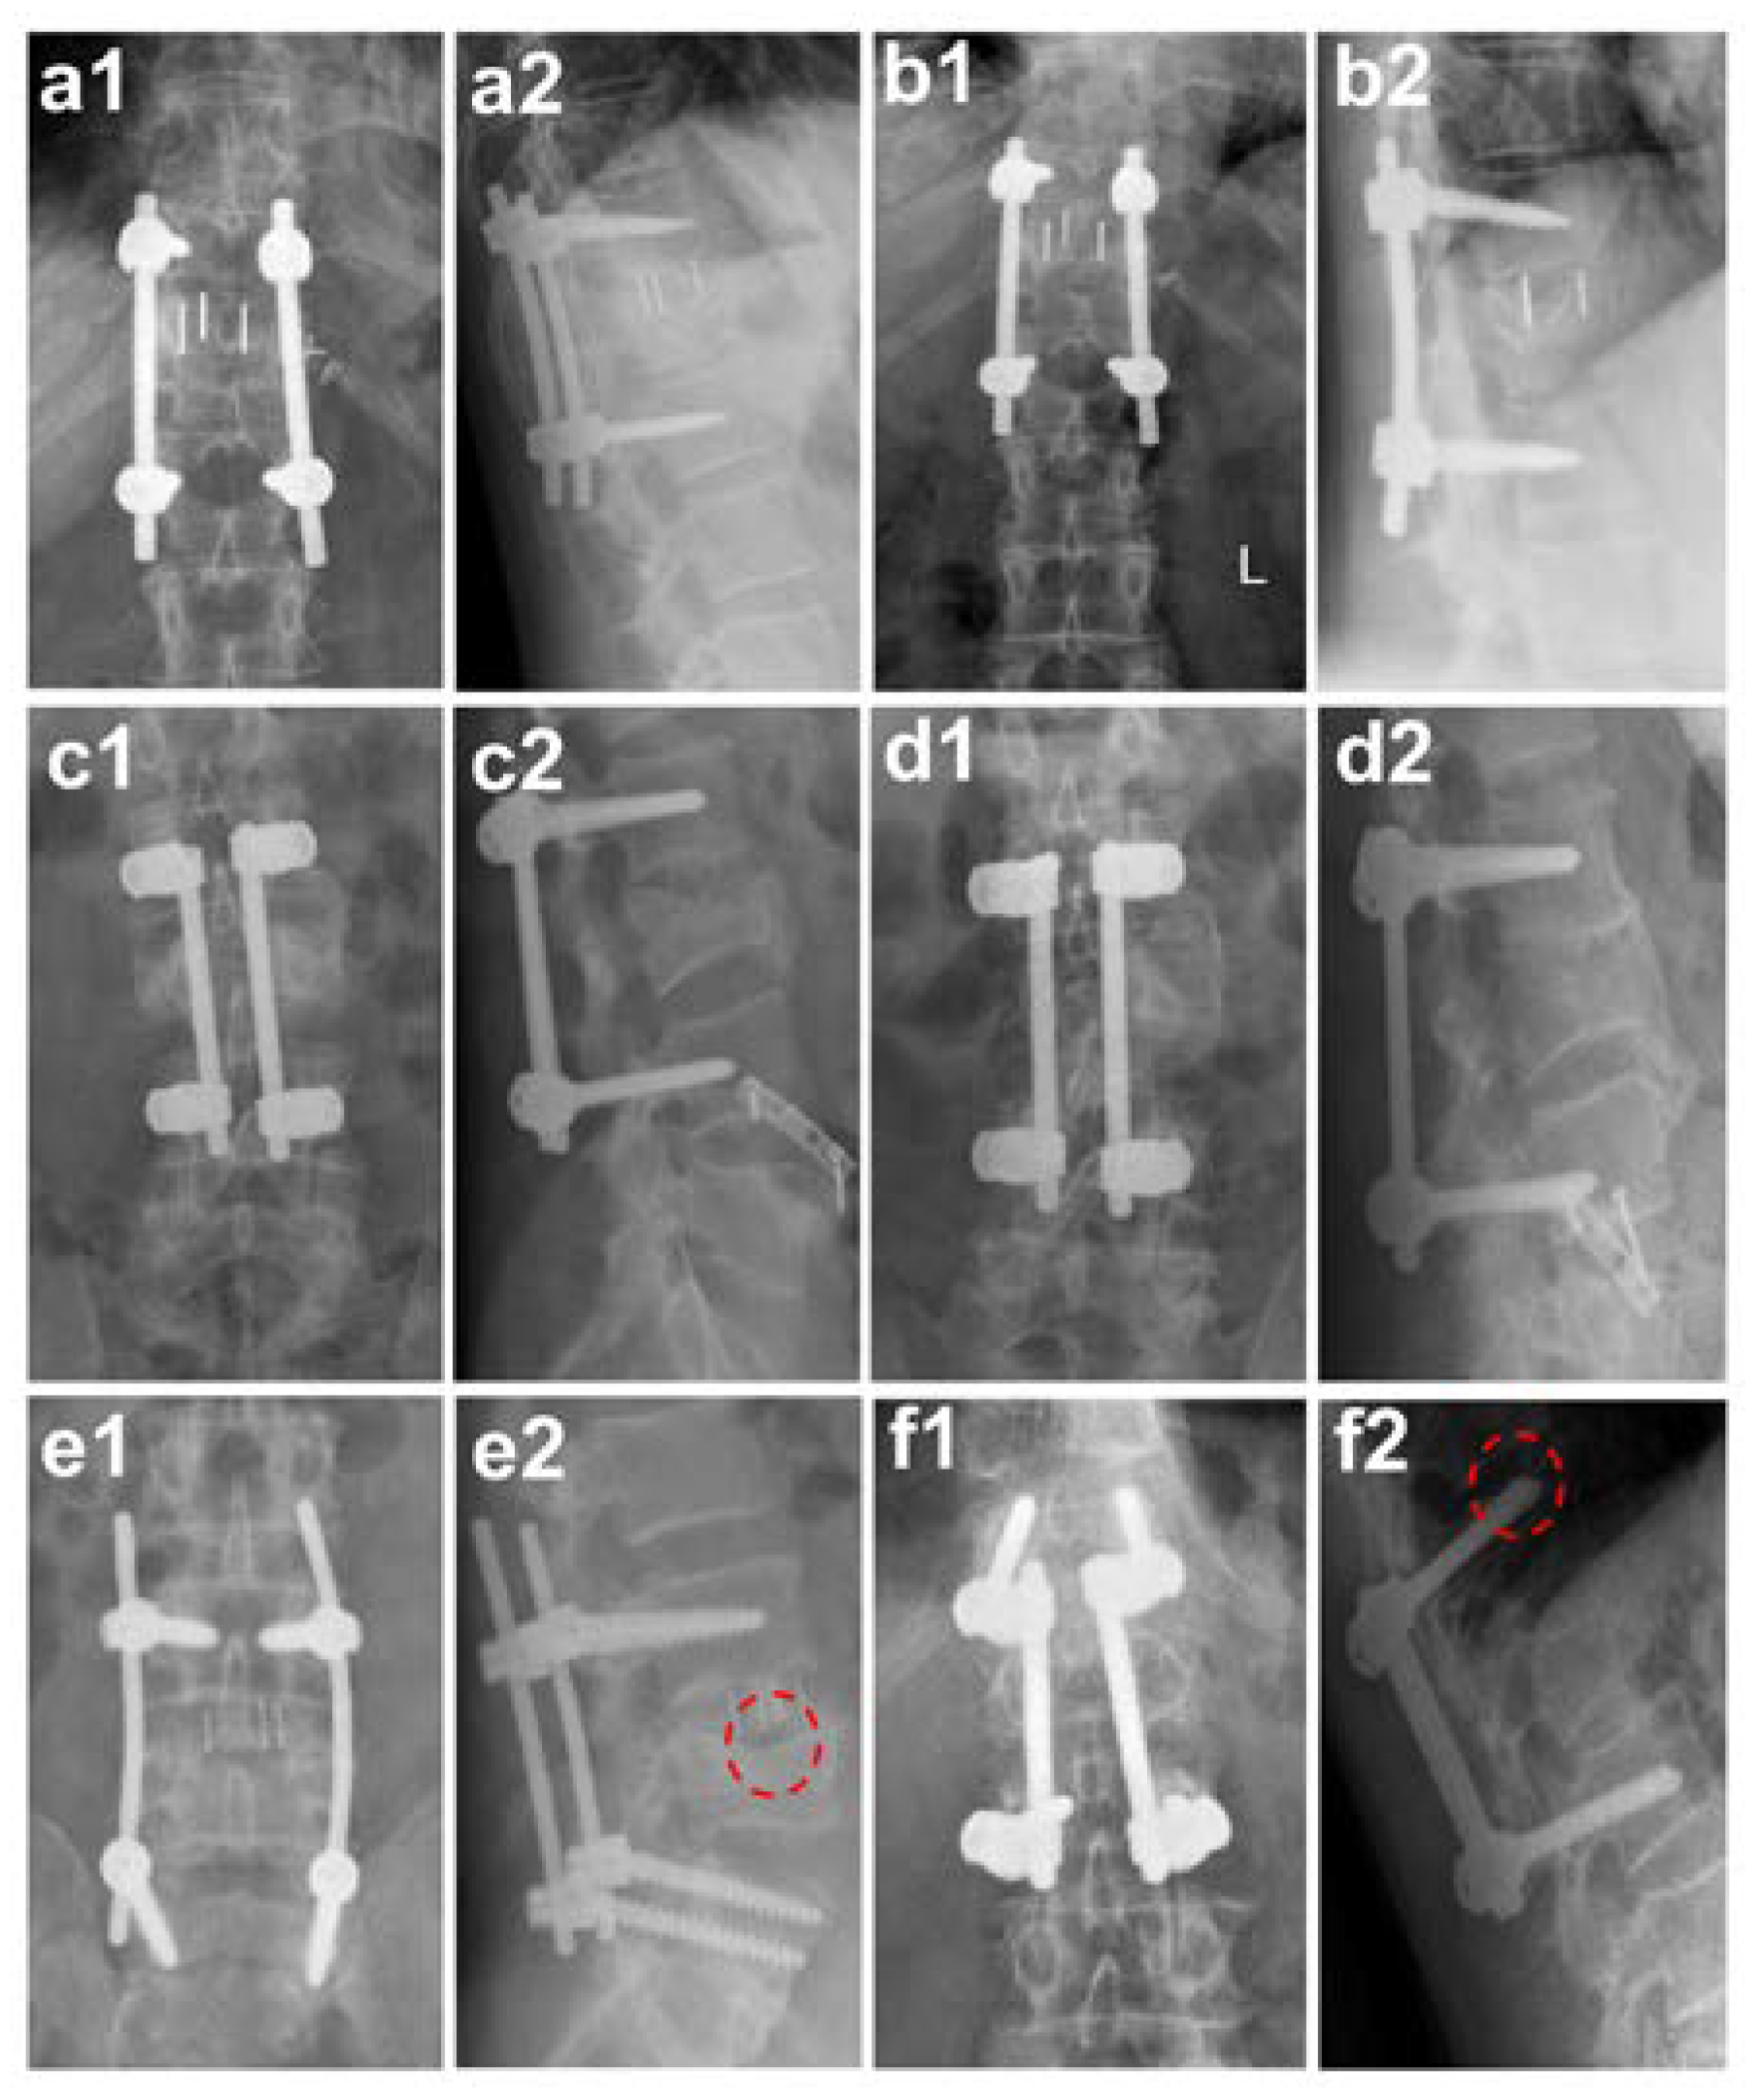

Inclusion criteria for the reported retrospective cohort study with observing character were defined by a patient collective who received a monosegmental fusion at the thoracic and lumbar spine due to a traumatic injury and with complete follow up records over a minimum of one year. The study was carried out at The University Medical Center in the period 2008–2018 with thoracic and lumbar spine surgery for patients with cage implantation (see Figure 1a,b) and for a six year period (2008–2013) for a patient collective with autologous tricortical pelvic bone grafts (see Figure 1c,d) with regular follow-up examinations after the surgery procedure. Based on these criteria, a patients collective treated with monosegmental cages, those with a traumatic fracture in the area of the thoracic vertebrae and lumbar vertebrae, were selected. They had been subjected to a ventral monosegmental fusion by rather a cage (MonoliftXP TL®, Aesculap AG, Tuttlingen, Germany) or pelvic bone graft. Of these 103 patients, 12 patients (mean age: 54.08; 5 females and 7 males) treated with cages were included in the study, as were 34 patients (mean age: 42.18; 11 females and 23 males) out of the 95 patients treated with autologous pelvic bone grafts.

Since standard classifications on the bony fusion of caging and autologous pelvic bone graft are not yet established, we assessed the approximate fusion status via X-ray analysis. These radiological controls included an antero-posterior view of the spine with an additional lateral projection and they were evaluated by two experienced spine surgeons. The status of the patients was considered stable, and bones were judged as probably fused, when the following radiological signs were detectable: (1) loosening signs such as hypodense areas around the implant, bone lysis, hypertrophic callus, or delayed fracture healing were absent after 12 months [10]; (2) detectable callus formation when bridging bone connecting the adjacent vertebral bodies was detected either through or around the implants and no radiolucency was seen, (3) visible bridging trabecular bone either crossing the cage or surrounding it, which were detected on anterior–posterior and lateral views of the radiographs [11]; (4) lack of substantial sclerotic changes in the recipient bone bed; and (5) vertebral body translation of <3 mm on lateral radiographs [11]. If these radiological signs were absent, it was classified as non-fused (see Figure 1e,f).

Figure 1. Fusion and non-fusion after surgical care. (a,b) Cage implantation; (c,d) autologous pelvic bone graft and subsequent bony fusion; (a1,b1) spine radiologically in anterior-posterior projection at different time points ((a1) post-operative; (b1) follow-up after one year); (a2,b2) spine radiologically in lateral projection at different time points ((a2) post-operative; (b2) follow-up after one year); (c1,d1) spine radiologically in anterior-posterior projection at different time points ((c1) post-operative; (d1) follow-up after one year); (c2,d2) spine radiologically in lateral projection at different time points ((c2) post-operative; (d2) follow-up after one year); (e,f) are controls after one year post-operative and show examples of non-fusion: (e) shows a hypodense area around the implanted cage ((e1) anterior-posterior projection and (e2) lateral projection; see hypodense area marked with dashed circle in red); (f) shows the loosening and cutting-out of the screws in the area of the cover plate of the vertebral body after autologous pelvic bone graft insertion ((f1) anterior-posterior projection and (f2) lateral projection; see cutting-out of the screws marked with dashed circle in red).